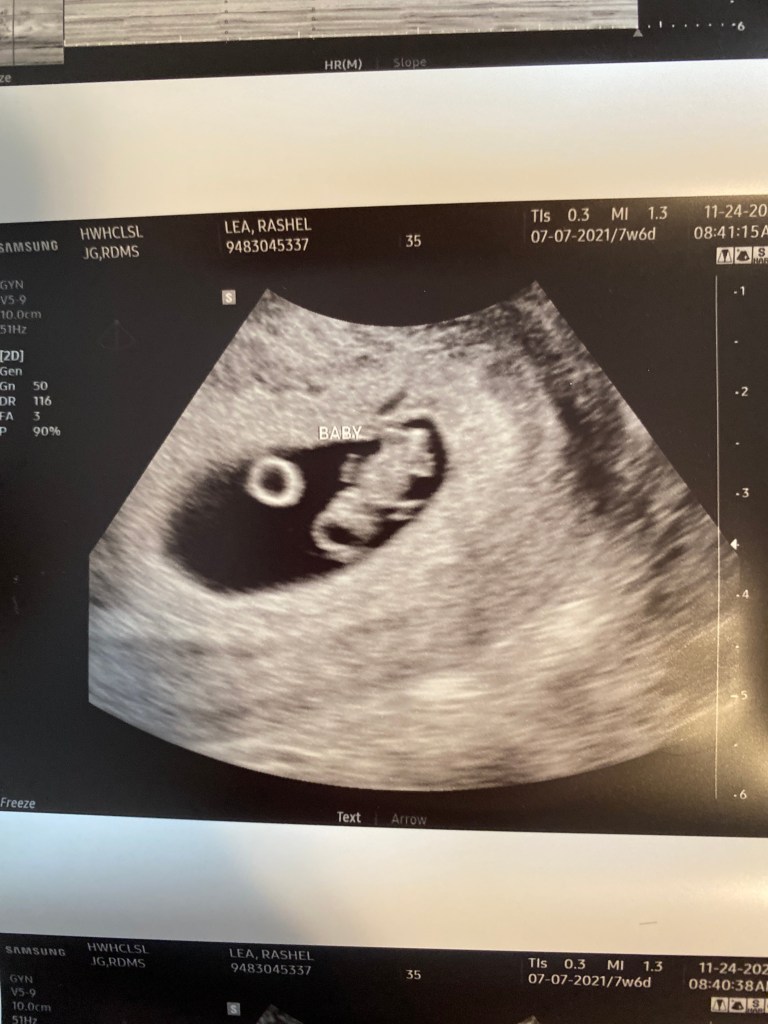

Well almost I’ll be 8 weeks tomorrow! So today I went in for another ultrasound and I’m always a little nervous before ultrasounds because well it’s early and so many things sadly could go wrong. Plus since I don’t really get many pregnancy symptoms I don’t actually feel much different. I’m always so excited once I can see the baby looks bigger and see the fluttering heartbeat! That will never not amaze me. It’s so incredible and beautiful all at the same time. Just weeks ago they put this tiny ball of cells baby into me and now he has tiny arm and leg buds starting to form! It’s just so hard to believe it can all happen so fast. The love I feel for these little babies is also so amazing to me. You just can’t help it. I have prayed for this little guy before he was ever even in me. I prayed he would thaw out perfectly and that he would be comfortable in my fluffy uterine lining. He’s just a baby miracle and I feel so blessed and lucky to help.

While the ultrasound technician was checking everything I was joking and asked if he was head down yet. 😂 Turns out he is!!! Woohoo 🙌 obviously this boy has plenty of time to wiggle and move about but it was so funny to me since his big brother came out breach! I have literally delivered babies every way possible at this point. I kinda think it’s cool. Oh also his heart rate went up to 163 so that’s great also.

This is what baby B has been up to 🥰